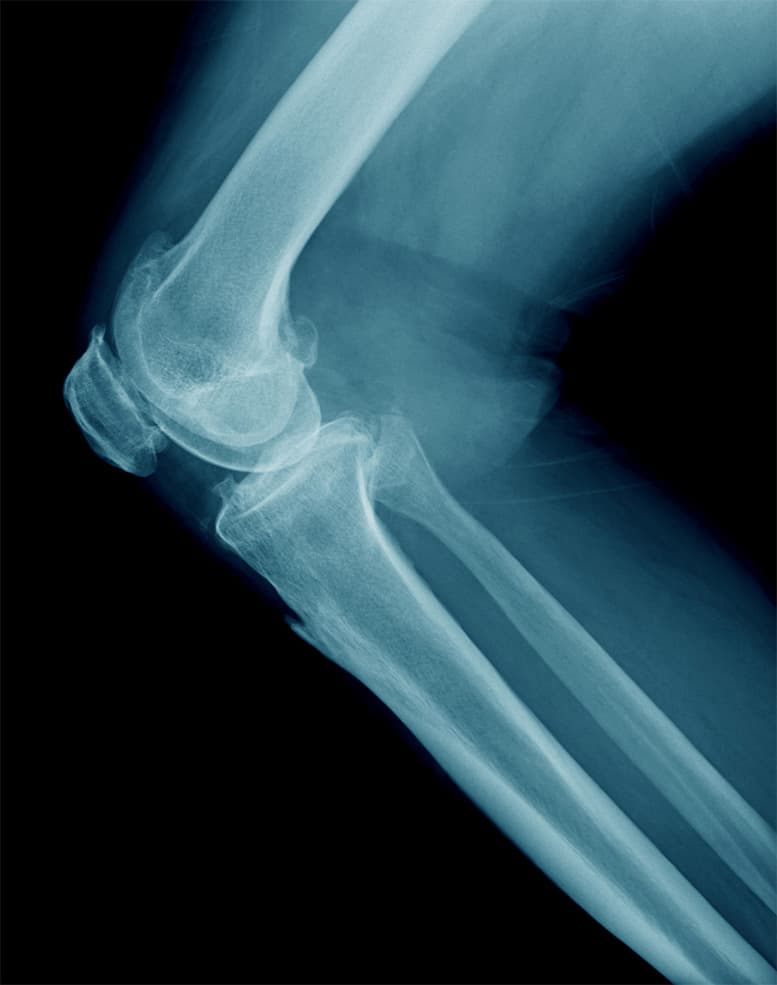

Specialista in patologie del ginocchio, come la gonartrosi e le lesioni meniscali, e dell'anca, con particolare attenzione alle tecniche di chirurgia protesica, inclusa l'innovativa via anteriore mininvasiva.